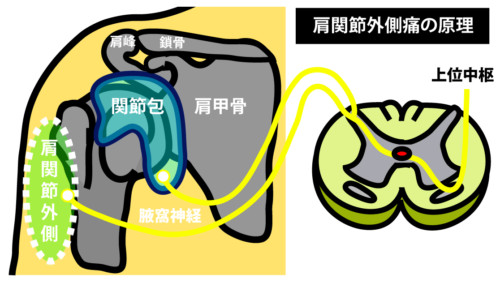

② 肩関節拘縮(関節包の縮小)

後方~下方関節包が短縮→骨頭が潜れず最終挙上で伸張痛。

伸張刺激は腋窩神経経由で肩外側痛として誤認されやすい(関連痛)。

⑤ 腋窩神経障害(四角間隙症候群など)

機序・所見

腋窩神経は四角間隙(小円筋・大円筋・上腕三頭筋長頭・上腕骨)を通過。圧迫で三角筋・小円筋の筋力低下+肩外側の知覚低下。